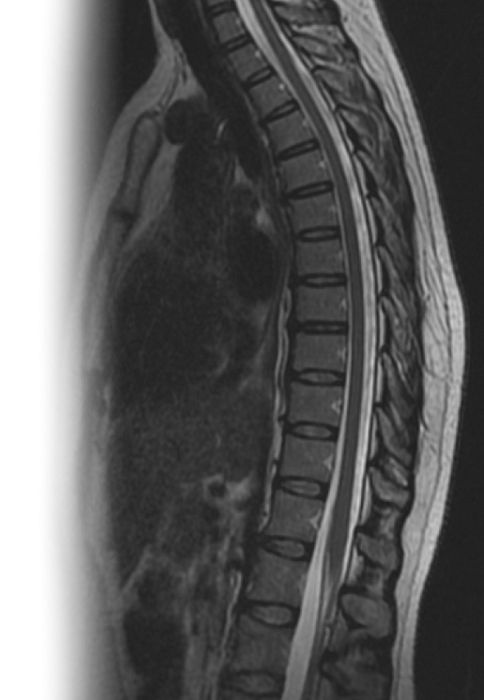

МРТ грудного отдела позвоночника

Магнитно-резонансная томография грудного отдела позвоночника – важный метод исследования, который позволяет оценить состояние грудного отдела позвоночника.